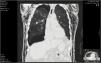

After a tractor accident resulting in significant thoracic trauma, a 79-year-old man was brought to the emergency room. The patient, with a history of atrial fibrillation and anticoagulation, also had obstructive lung disease and lung emphysema. Primary evaluation revealed exuberant cervical, thoracic, and abdominal emphysema. A CT scan was performed that documented the massive subcutaneous emphysema and pneumothorax at the right hemithorax. A right-sided chest tube was inserted, and orotracheal intubation was carried out due to respiratory failure. The patient was subsequently admitted in the intensive care unit.